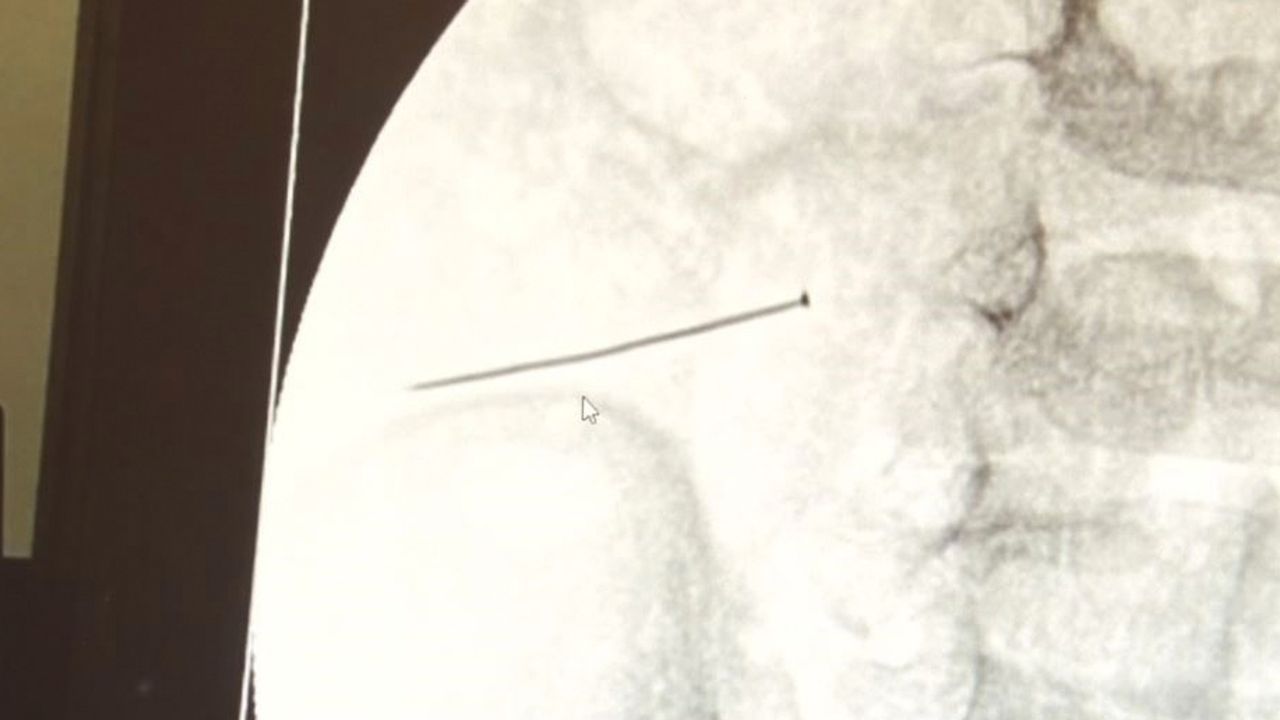

Öte yandan, yaklaşık 3 santimlik toplu iğne filme yansıyan görüntüsüyle gözler önüne serildi.

İstanbul’da 2 yaşındaki çocuk iddiaya göre toplu iğne yuttu sonrasında adeta karın ağrısıyla yerinde duramaz hale geldi. Babaanne, küçük çocuğun şikayetleri üzerine Şehit Prof. Dr. İlhan Varank Sancaktepe Eğitim ve Araştırma Hastanesi’ne götürdü. Burada yapılan tetkiklerde 2 yaşındaki çocuğun ince bağırsağında yaklaşık 3 santimlik toplu iğne olduğu ve bağırsağı deldiği belirlendi. Görüntülemeler sonrası 30 Ekim akşamı Çocuk Cerrahisi Kliniği Eğitim ve İdari Sorumlusu Doç. Dr. Sefa Sağ ve ekibi hemen ameliyata girdi. Başarılı operasyonla iğne olduğu noktadan alınırken aile de rahat bir nefes aldı. Doç. Dr. Sağ ise taburcu edilen hastasının durumuna ilişkin bilgi verirken yabancı cisim yutmalarına karşı ailelere önemli uyarılarda bulundu.

Çocuklarda yabancı cisim yutulmasına yönelik konuşan ve hastasına ilişkin bilgi veren Doç. Dr. Sefa Sağ, "Soluk borusuna kaçması durumunda çocuğun Allah göstermesin ölümüyle veya ömür boyunca yatağa bağımlı kalmasıyla neticelenebilecek sonuçlar doğurabiliyor. Yutulması durumunda da gastrointestinal sistemin herhangi bir yerine takılmadığı müddetçe ekseriyâ yabancı cisimlerin dışarıya çıkmasını bekliyoruz. Yabancı cisim yutulmasını 2 grupta inceleyebiliriz. Sıvı ve katı cisimler olarak sıvı; evde kullanılan kimyasal temizlik malzemelerinin yutulması çok ciddi problemler oluşturabilmekte. Ağızda, yemek borusunda ve midede yanıklar meydana getirebilmekte. Uzun dönemde çocukların hayat kalitesini oldukça etkileyen sonuçlar doğurabilmekte. Katı cisimlerden de ekseriyâ kendiliğinden çıkmasını bekleriz ancak böyle delici, kesici aletlerin yutulmasında ise herhangi bir bağırsağın veya gastrointestinal sistemin bir parçasında delinmeler meydana getirebiliyor. Bu çocuğumuzda da aynen böyle bir hadise meydana gelmişti. Sanırım 1 gün önce ailenin yuttuğunu tahmin ettiği bir yabancı cisim; toplu iğne. Ertesi gün bağırsakta delinmeyle sonuçlanmış ve çocukta da ciddi semptomlar meydana getirmişti. Bu şekilde hasta bize başvurdu. Tetkikler sonucunda yabancı cismi tespit ettik, semptomları ve bulgularına göre de çocuğu ameliyata aldık. Yaklaşık 3 santim boyunda bir toplu iğnenin ince bağırsağı deldiğini, ince bağırsaktaki içeriğin de karın içerisine dolduğunu gördük. Ameliyatı başarılı bir şekilde tamamladık, yaklaşık 1 saat süren bir ameliyattı" dedi.